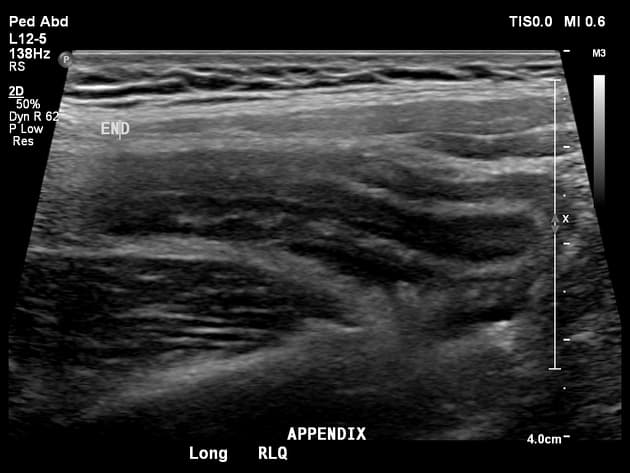

Tìm thấy giãn phình phụ thuộc với thành dày, kích thước khoảng 1,4 cm. Phồng lên của thành tá tràng gần đó.

Có sự gián đoạn trên thành của phụ thuộc ở phần gốc với dịch xung quanh, rất đáng ngờ về tình trạng vỡ phụ thuộc. Dịch nhẹ hiện diện xung quanh phụ thuộc và viêm ở mô mỡ xung quanh.

THẢO LUẬN: Vì siêu âm không liên quan đến bức xạ ion hóa và là phương thức tốt hơn cho các tình trạng phụ khoa, nó được khuyến nghị là phương thức hình ảnh ban đầu ở trẻ em, phụ nữ trẻ và trong thời kỳ mang thai. Nó có độ nhạy và đặc hiệu rất cao trong chẩn đoán viêm phụ thuộc. Phương pháp nén có cấp độ được mô tả bởi Puylaert là phương pháp tiêu chuẩn cho đánh giá siêu âm về viêm phụ thuộc cấp. Áp lực từ từ, nhẹ nhàng và duy trì ở điểm đau và nhạy cảm tối đa giúp trình diễn phụ thuộc một cách dễ dàng. Nếu bệnh nhân không cho phép nén, chúng ta có thể sử dụng kỹ thuật của Baldisserotto bằng cách thay đổi vị trí của bệnh nhân để di chuyển các vòng ruột. Việc xác định vị trí của tá tràng rất quan trọng, giúp làm hướng dẫn trong việc tìm kiếm phụ thuộc. Trong trường hợp này, cả hai phương pháp đều được sử dụng vì bệnh nhân béo phì. Việc quay bệnh nhân sang vị trí nằm nghiêng trái ngay lập tức đã trình diễn phụ thuộc giãn. Giãn phụ thuộc hơn 6mm, dịch xung quanh và hạch to lên xác nhận chẩn đoán viêm phụ thuộc. Bệnh nhân cũng trải qua đau nhức nặng khi thực hiện siêu âm.

Viêm ruột thừa